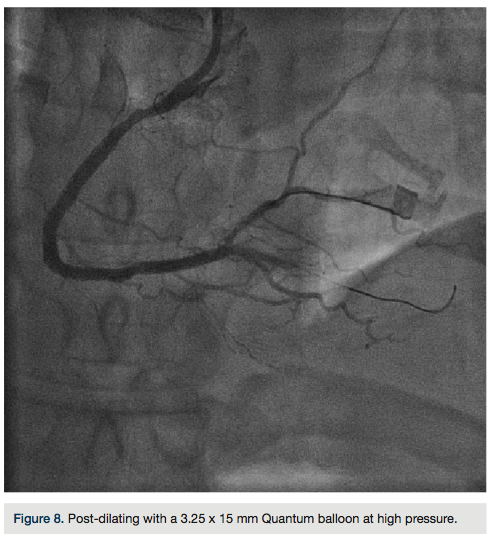

There was transient loss of flow in the posterior left ventricular branch (PLV), which was wired with a Fielder XT wire, and then changed out for a Pilot wire through an over-the-wire balloon (Figure 7). We exchanged for a Runthrough wire into the distal posterior descending coronary artery (PDA). The Corsair was removed from the collateral, and we took the guide and wire from the left system. Two additional 3.0 x 28 mm Promus drug-eluting stents were placed distally prior to the bifurcation. After stent placement, there was good flow in the distal vessel. A gap in between the stents was covered with a 3.0 x 8 mm Promus drug-eluting stent. We then

post dilated with a 3.25 x 15 mm Quantum balloon (Boston Scientific) at high pressure (Figures 8-9). Because of a pseudo lesion in the proximal vessel, we exchanged out for a Judkins right (JR) 4 guide and gave 200 mcg intracoronary (IC) nitroglycerin. Angiography revealed TIMI-3 flow in the vessel without any perforation or embolization (Figure 10). The patient tolerated the procedure well. The guide was removed and a TR Band (Terumo) was placed over bilateral radials. The patient has done well clinically, and is approximately 6 months post PCI with excellent functional capacity and no ischemic symptoms.